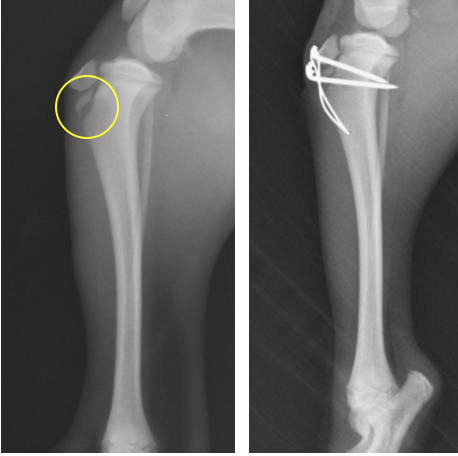

脛骨粗面のみの骨折です。ここも膝蓋靭帯が近位に引っ張る力が常にかかるため、ピンとテンションバンドワイヤーによって固定しています。